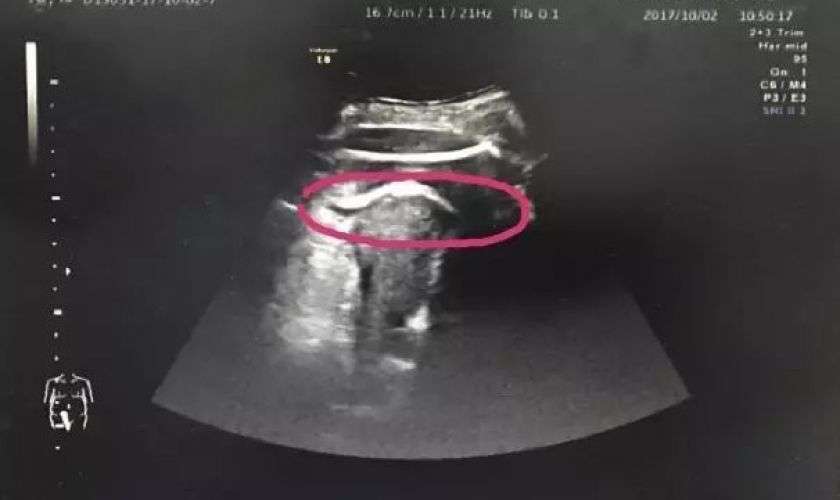

Женщина на сносях едва не умерла после мощного пинка своей еще неродившейся дочери. Находящийся в утробе ребенок ударил ее настолько сильно, что на стенке матки образовалась рана. Врачам пришлось делать экстренное кесарево сечение. В настоящий момент мать и дочь находятся в больнице, их здоровью ничего не угрожает.

Нерожденная дочь разорвала утробу матери ударом изнутри